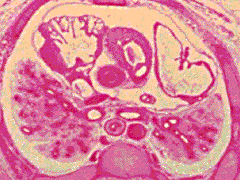

D5:

R, L primary bronchi. R anterior and posterior

segmental bronchi coming off R superior lobe

bronchus. L, R pulmonary arteries. Hilar

attachments of lungs to mediastinal tissues - note

extent of R, L pleural cavities.